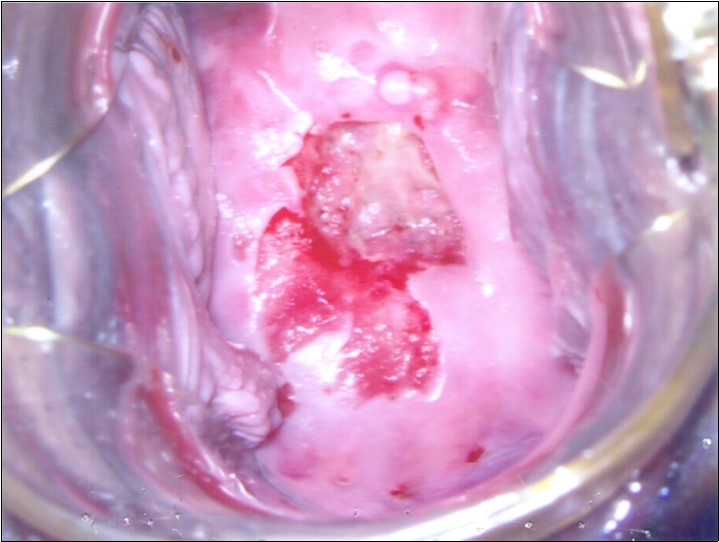

At initial presentation, colposcopy was unsatisfactory due to inadequate visualisation of the transformation zone. (Figure 1) Severe cervico-vaginitis was seen, with frothy white discharge and contact bleeding. A small focus of aceto-white epithelium was seen at the 1 o’clock region surrounded by peeling, friable epithelium. HPV DNA test, as well as cervical punch biopsy of the focus of aceto-white epithelium were taken.

Figure 2a.Repeat colposcopy (low magnification)